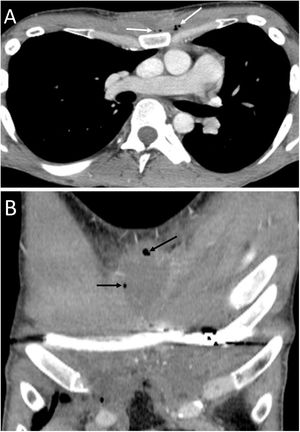

Pericardial locationPneumopericardium (PPC) is caused by invasive procedures (thoracentesis, endotracheal intubation, thoracotomy, etc.), pericarditis, chest trauma, barotrauma and fistulas with air-borne structures (bronchial tree, gastrointestinal tract, and pleural or peritoneal spaces).19,20 In pneumothorax and PM due to barotrauma or blunt trauma, it has been suggested that the aetiopathogenesis could be the rupture of the alveolar walls with air passing towards the hila and/or the pleura, dissecting the peribronchovascular space. If this air spreads around the pulmonary veins and arteries, it can reach the pericardium. Another possible cause of air in the pericardium in chest trauma would be direct communication with the pleura or tracheobronchial tree through a pericardial rupture or tear.19 Most cases of PPC are due to iatrogenesis or trauma, spontaneous PPC being very rare.20 In the case of pulmonary neoplasia (Fig. 7), the possible routes are: direct invasion of the necrotic tumour that causes a bronchopericardial fistula, trauma due to bronchoscopy or thoracentesis, and rupture to the pericadium of a focus of necrosis.20

A 53-year-old man with squamous cell carcinoma of the lung presented with chest pain, fever and productive cough. A) The chest X-ray showed a lung mass in the left upper lobe (black asterisk) and pneumopericardium (white arrows). B and C) Computed tomography showed progression of the upper left lung mass (asterisk) and pneumopericardium secondary to the direct extension of the tumour to the pericardium (white arrows).

It must be remembered that: chest X-ray shows air around the cardiac silhouette, limited superiorly by the lower border of the aortic arch, without extension around the trachea, bronchi or cervical region. CT enables confirmation of the diagnosis and identification of the possible cause. Treatment will be conservative if the pneumopericardium is small and the patient is stable and asymptomatic.21